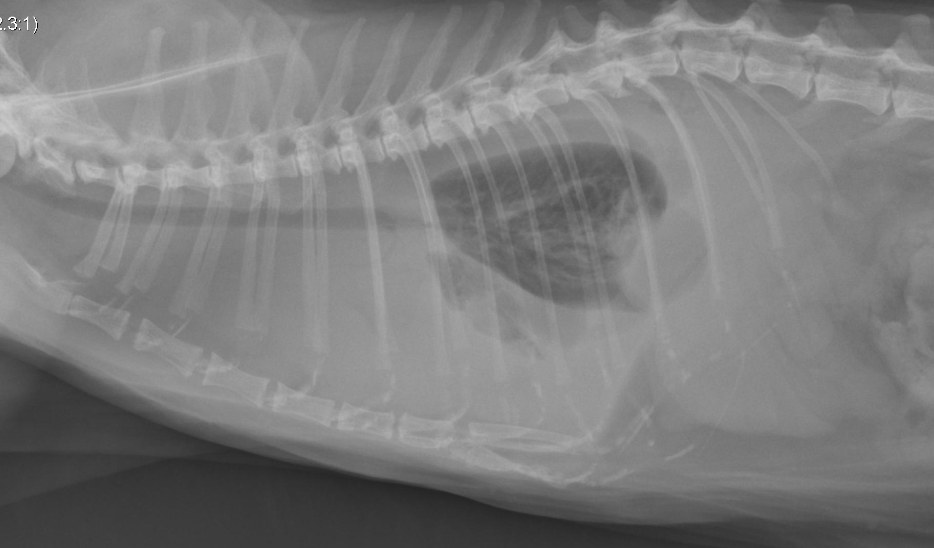

why can you only see the the lung masses in the DV radiograph and not in the VD radiograph?

on the VD, the dorsal lung is against the table and has become (dependent), meaing it’s been squished and is no longer full of air. This makes it appear as soft tissue rather than air, and the soft tissue masses are effeced and do not show up. On the DV, the ventral lung has now become squished and the dorsal lung is airated, making it a different opacity than the lung masses so they appear on the radiograph.